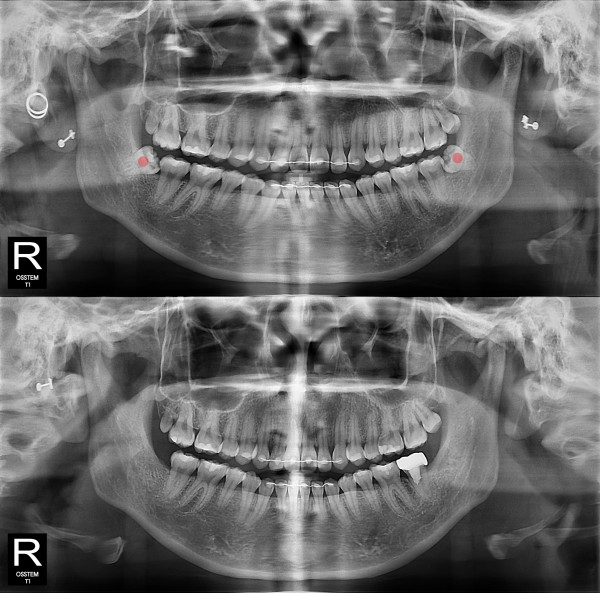

智齿拔除 严重龋坏的智齿

b047bd763797d0ee5fe0c71c12970e9f_1766119681_4736.jpg